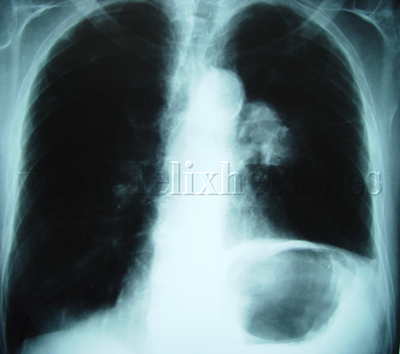

Cáncer de pulmón